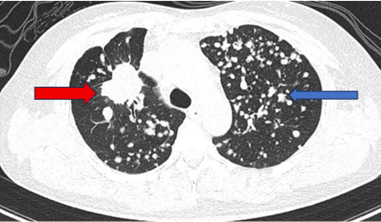

Hình ảnh chụp cắt lớp vi tính ngực: Dải xẹp phổi rải rác thuỳ dưới hai phổi. Nhu mô còn lại đồng nhất, không thấy tổn thương khu trú hoặc lan tỏa. Không thấy tổn thương hình mờ dạng lưới. Không thấy giãn phế quản – phế nang.

Hình 6. Phim chụp cắt lớp vi tính chưa phát hiện tổn thương thứ phát.